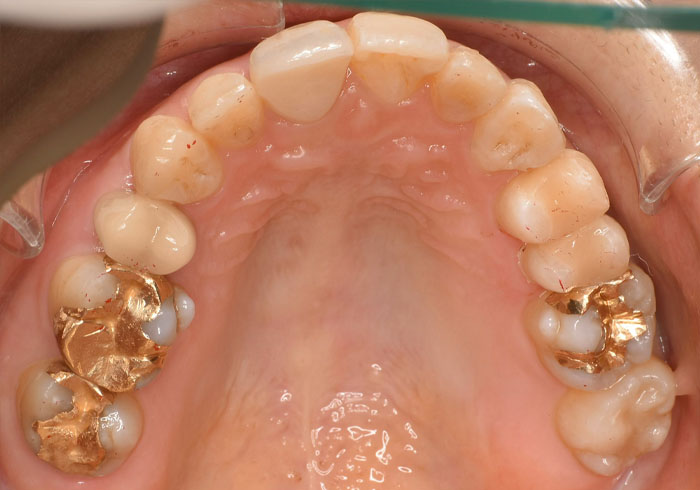

口腔内写真

治療前

マウスピース矯正 マウスピース矯正 マウスピース矯正